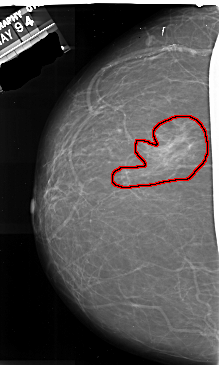

A_1014_1.LEFT_CC

LEFT_CC LINES 6931 PIXELS_PER_LINE 4156 BITS_PER_PIXEL 16 RESOLUTION 42 OVERLAY

FILE: A_1014_1.LEFT_CC.OVERLAY

TOTAL_ABNORMALITIES 1

ABNORMALITY 1

LESION_TYPE MASS SHAPE IRREGULAR MARGINS ILL_DEFINED

ASSESSMENT 4

SUBTLETY 4

PATHOLOGY MALIGNANT

TOTAL_OUTLINES 1

BOUNDARY